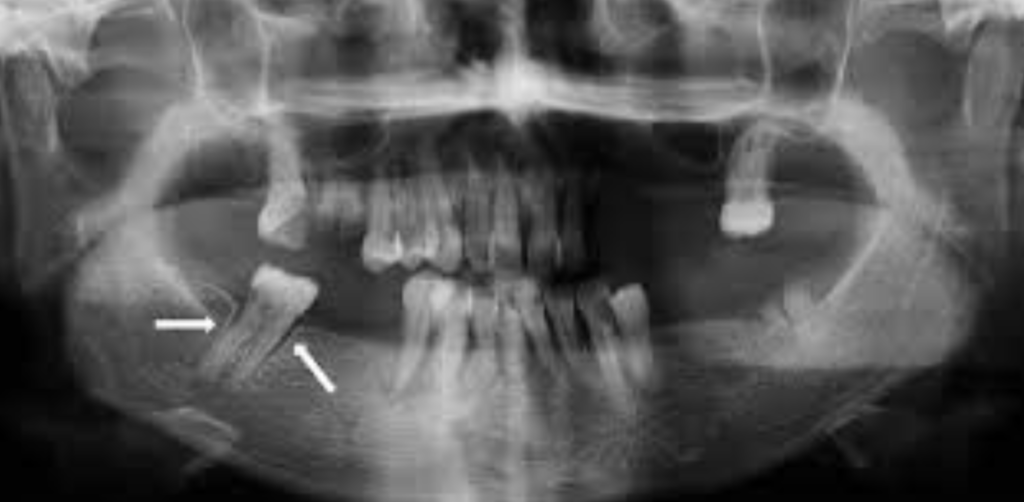

Patiente : Nadia, 38 ans, secrétaire, sans antécédents médicaux notables. Consultation pour « gonflement de la joue » apparu progressivement depuis plusieurs mois.

Présentation : À l’inspection, tuméfaction vestibulaire en regard de la 22 (incisive latérale supérieure gauche). La patiente rapporte une légère mobilité de ses dents antérieures. Les tests de vitalité sont négatifs sur la 22. La dent présente une couronne céramique.

Problématique identifiée : La radiographie panoramique révèle une image radioclaire homogène bien délimitée de 14 mm, appendue à l’apex de la 22, avec un liseré osseux périphérique dense. La dent adjacente (21) est légèrement déplacée. Diagnostic retenu : kyste péri-apical (taille > 10 mm, contours nets, déplacement dentaire quasi-pathognomonique).

Prise en charge :

- Consultation spécialisée en chirurgie orale

- Traitement endodontique préalable de la 22 (élimination de la source infectieuse)

- Kystectomie chirurgicale avec énucléation complète de la poche kystique sous anesthésie locale

- Examen histopathologique de la pièce chirurgicale pour confirmation du diagnostic et exclusion d’une pathologie tumorale

Résultat attendu : Fermeture progressive de la cavité osseuse sur 6-12 mois. Suivi radiographique semestriel. Ce cas illustre l’évolution silencieuse des kystes et la nécessité d’un examen clinique régulier.